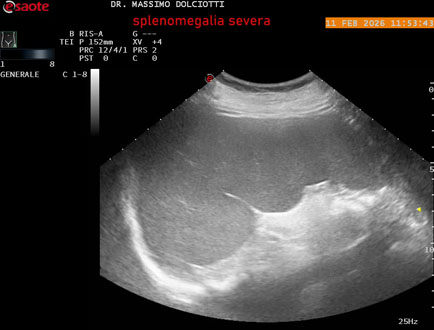

Data inserimento: 18/02/2026

Ecografia del: 11/02/2026

Strumento: Esaote MyLab Eight

Sonda: Conevx Multifrequenza 1-8 MHz

Età Paziente: F 68 anni

Motivazione dell'esame: follow up di splenomegalia.

Commento all'esame: le immagini ed il video documentano la milza con ecostruttura normale e morfovolumetria superiore alla norma, con diametro bipolare di 159 mm (v.n. 70-120 mm) ed area di sezione di 101 centimetri quadri (v.n. < 47 centimetri quadri).

Conclusioni: splenomegalia di severa entità (severe splenomegaly).